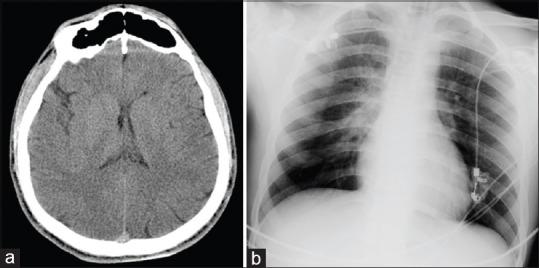

Butane is a commonly misused volatile agent, and a cause of intoxication. We present a case, who had a syncope and persistent ventricular fibrillation during the course of resuscitation. We discussed the management of this case in the intensive care unit and the accompanying difficulties in the light of the current literature.

https://cdn.ncbi.nlm.nih.gov/pmc/blobs/a49a/4563975/5f881098dea8/AER-9-273-g001.jpg